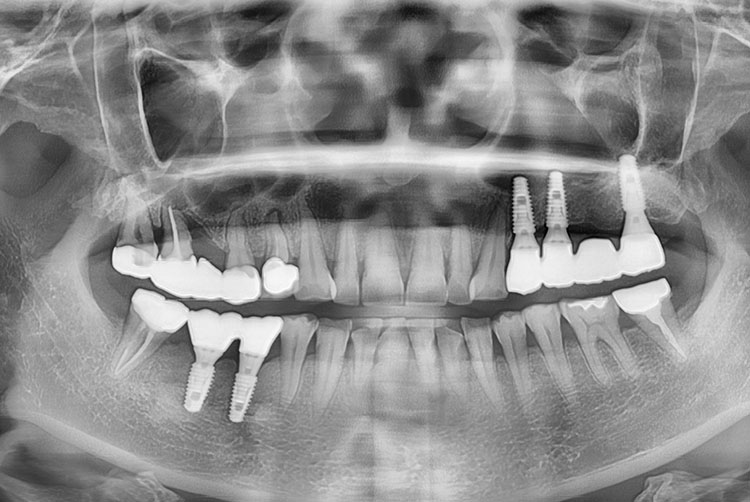

[임플란트] 임플란트

치료후 : 2021-12-31

세종치과는 많은 환자와 다양한 케이스를 바탕으로 항상 편안한 임플란트 수술을 제공하고자 노력하고,

오래동안 튼튼히 쓸 수 있는 임플란트 수술을 가장 큰 목표로 삼고 있습니다